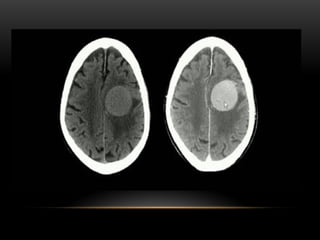

A primeira utilização operacional de um

tomógrafo computadorizado no mundo foi em

Atkinson Morley Hospital, em Londres, berço dos

estudos de Hounsfield. Além disso, o primeiro

equipamento de TC, só permitia a avaliação do

metabolismo cerebral ou de tumores do cérebro.

No Brasil, o primeiro

aparelho de tomografia

computadorizada foi

instalado no Hospital

Beneficência Portuguesa,

em São Paulo, no ano de

1977. A primeira avaliação

foi realizada em uma

mulher de 41 anos, com

um tumor no lobo frontal

esquerdo.

A primeira utilizaçãooperacional de um tomógrafo computadorizado no mundo foi em Atkinson Morley Hospital, em Londres, berço dos estudos de Hounsfield. Além disso, o primeiro equipamento de TC, só permitia a avaliação do metabolismo cerebral ou de tumores do cérebro.

No Brasil, oprimeiro aparelho de tomografia computadorizada foi instalado no Hospital Beneficência Portuguesa, em São Paulo, no ano de 1977. A primeira avaliação foi realizada em uma mulher de 41 anos, com um tumor no lobo frontal esquerdo.